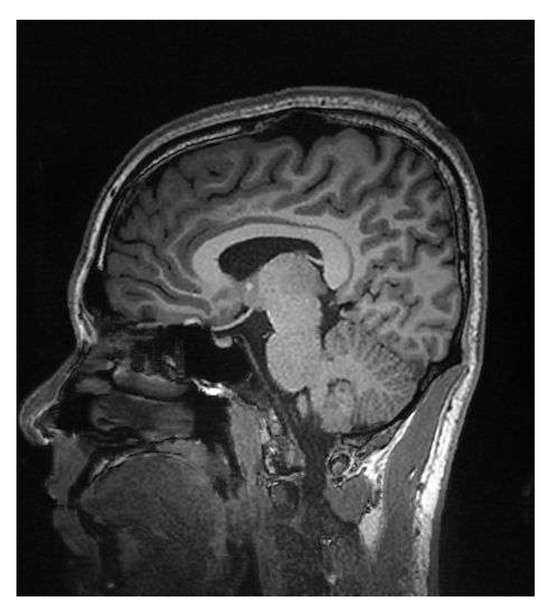

Figure 3 shows the original image that was used to obtain the simulated signal by applying the FFT, DCT, or wavelet transforms, thus simulating the signal received from a magnetic resonance imaging (MRI) system. The image was used with the four different proposed algorithms.

Figure 3. Reference image for the transforms.